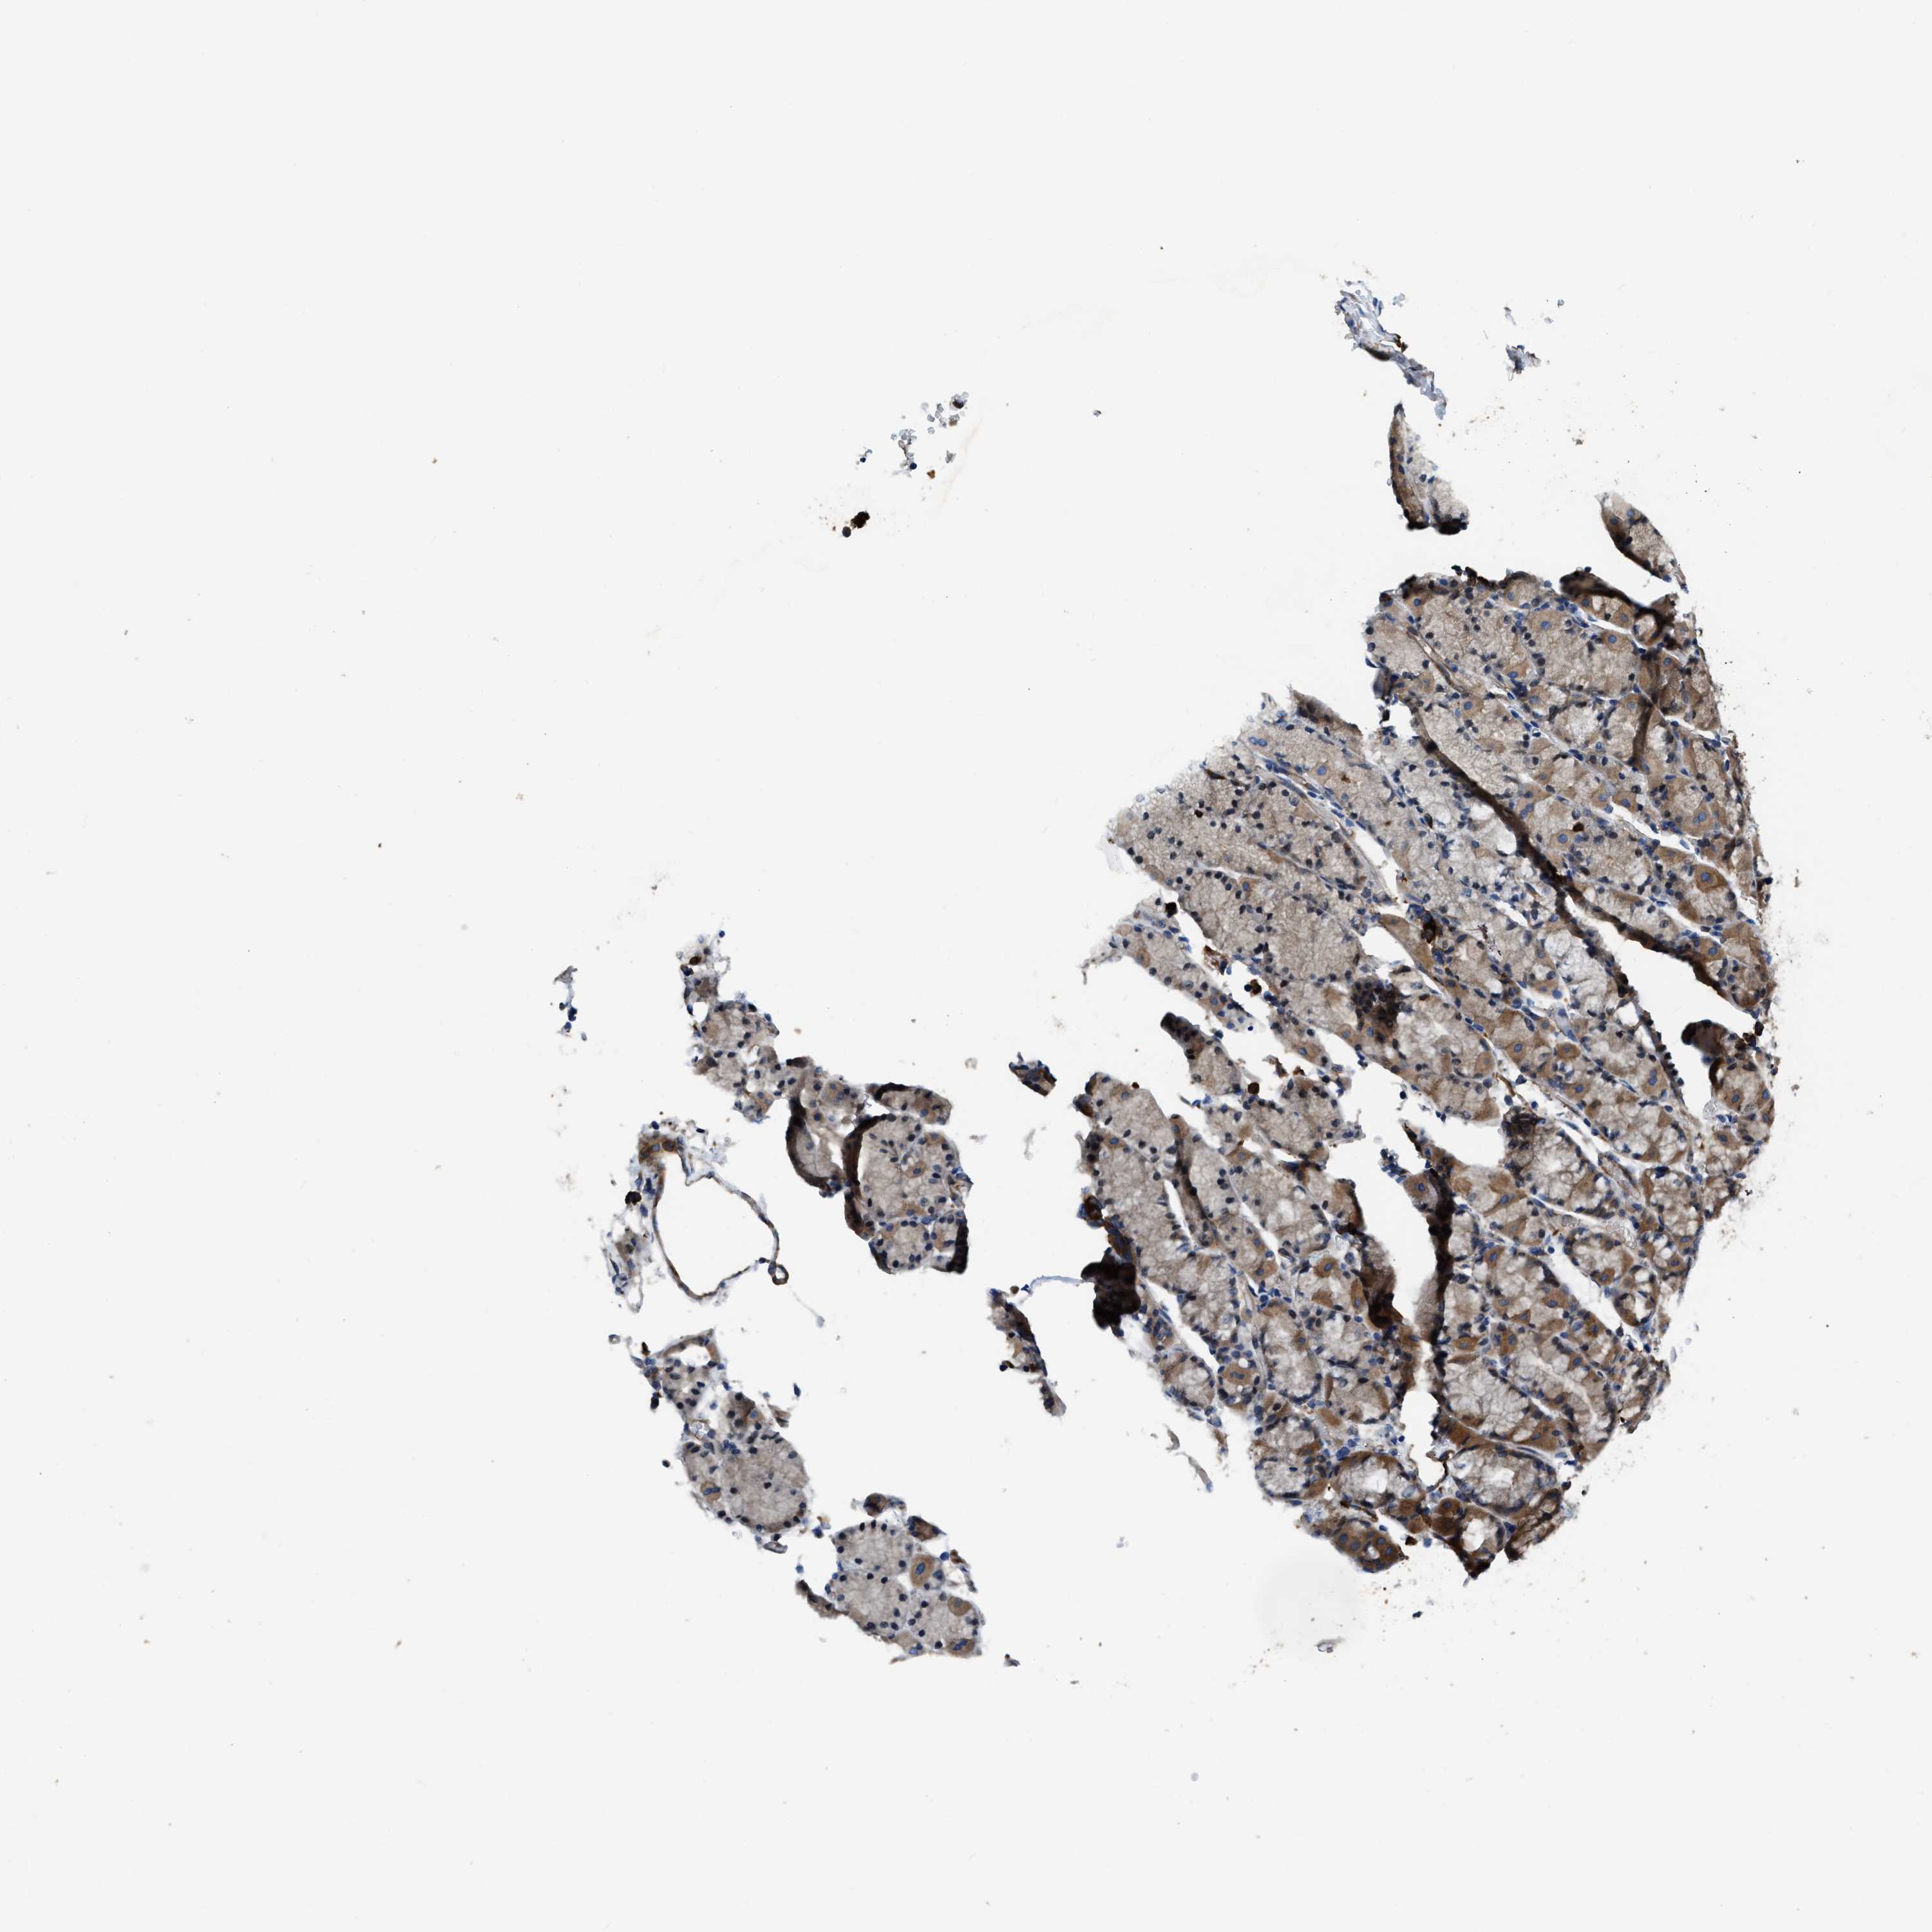

STOMACH 2 - Antibody stainingi

Antibody staining in the annotated cell types in the current human tissue is reported as not detected, low, medium, or high, based on conventional immunohistochemistry profiling in selected tissues. This score is based on the combination of the staining intensity and fraction of stained cells.

Each image is clickable and will lead to virtual microscopy that enables deeper exploration of all samples and also displays staining intensity scores, fraction scores and subcellular localization as well as patient and tissue information for each sample.

Antibody HPA018257

Glandular cells High